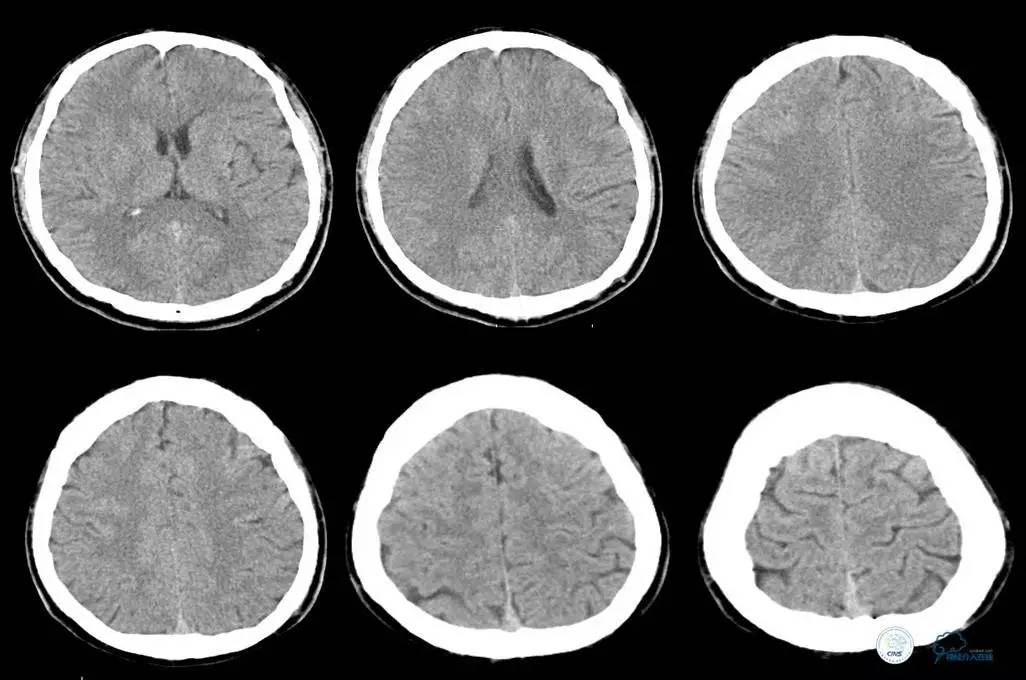

▼头CT

▼心电图:窦性心律,T波异常,心肌缺血改变。

2014年12月15日22时50分

患者言语不清、右侧肢体麻木无力等症状缓解,但四肢末端厥冷。心电监护示,SPO2为99%,P为65次/分,R为18次/分,BP为103/60mmHg。T为35.5℃。

初步诊断为短暂性脑缺血发作。追问患者家属病史,入院前曾有大汗,未进食,低血容量性休克不除外。补液纠正休克。

2014年12月16日00时20分

患者精神差,全身不适,右肩背部疼痛,呕吐3次,呕吐物为胃内容物,排便2次,无黑便,四肢末端冰冷较前缓解。心电监护示,SPO2为93%,P为62次/分,R为18次/分,BP为101/55mmHg。T为36.2℃。急查心肌酶示CK、CK-MB正常。

2014年12月16日05时

患者上腹部背部疼痛剧烈,予氯诺西康肌注。便血2次,鲜红色,量约30ml。心电监护示,SPO2为98%,P为67次/分,R为18次/分,BP为125/66mmHg。肝功能示,总蛋白为53g/L。肾功能示,尿素氮为10.6mmol/L,肌酐为170umol/L。血淀粉酶为113U/L。血常规示,血红蛋白为145.8g/L,中性粒细胞为14.33×109/L,白细胞为15.43×109/L,红细胞为4.42×1012/L。腹部超声示,胆囊结石。

辅助检查:头CT未见异常。